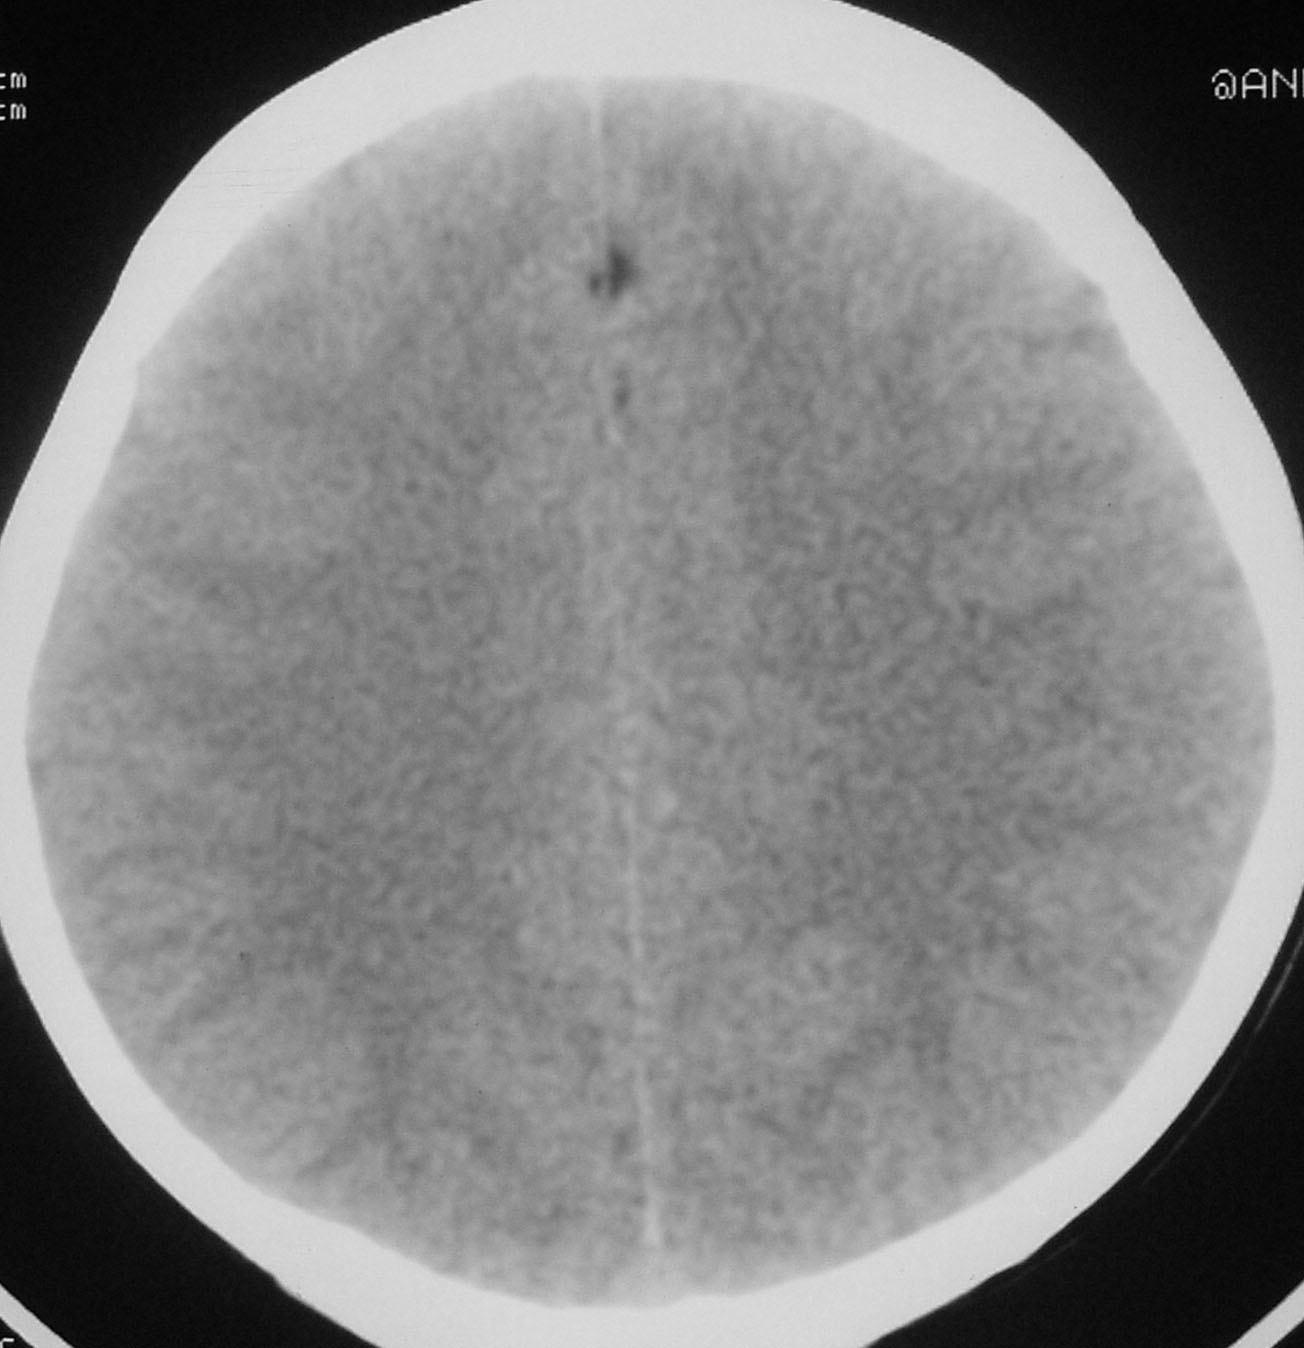

以下是引用余辉在2007-4-28 19:55:00的发言:[br]血管畸形?增强一下

以下是引用jw-830在2007-4-28 20:22:00的发言:[br]考虑血管畸形可能建议增强

以下是引用ysxyy在2007-4-29 21:14:00的发言:[br]像是假像,如果不放心可以偿试一下:[br]你用听眦线为基线扫一下,再用听眶线扫一下,就是说用不同的角度扫同一个地方;[br]看看有无变化,是不是有相同或相似的表现,即可鉴别;